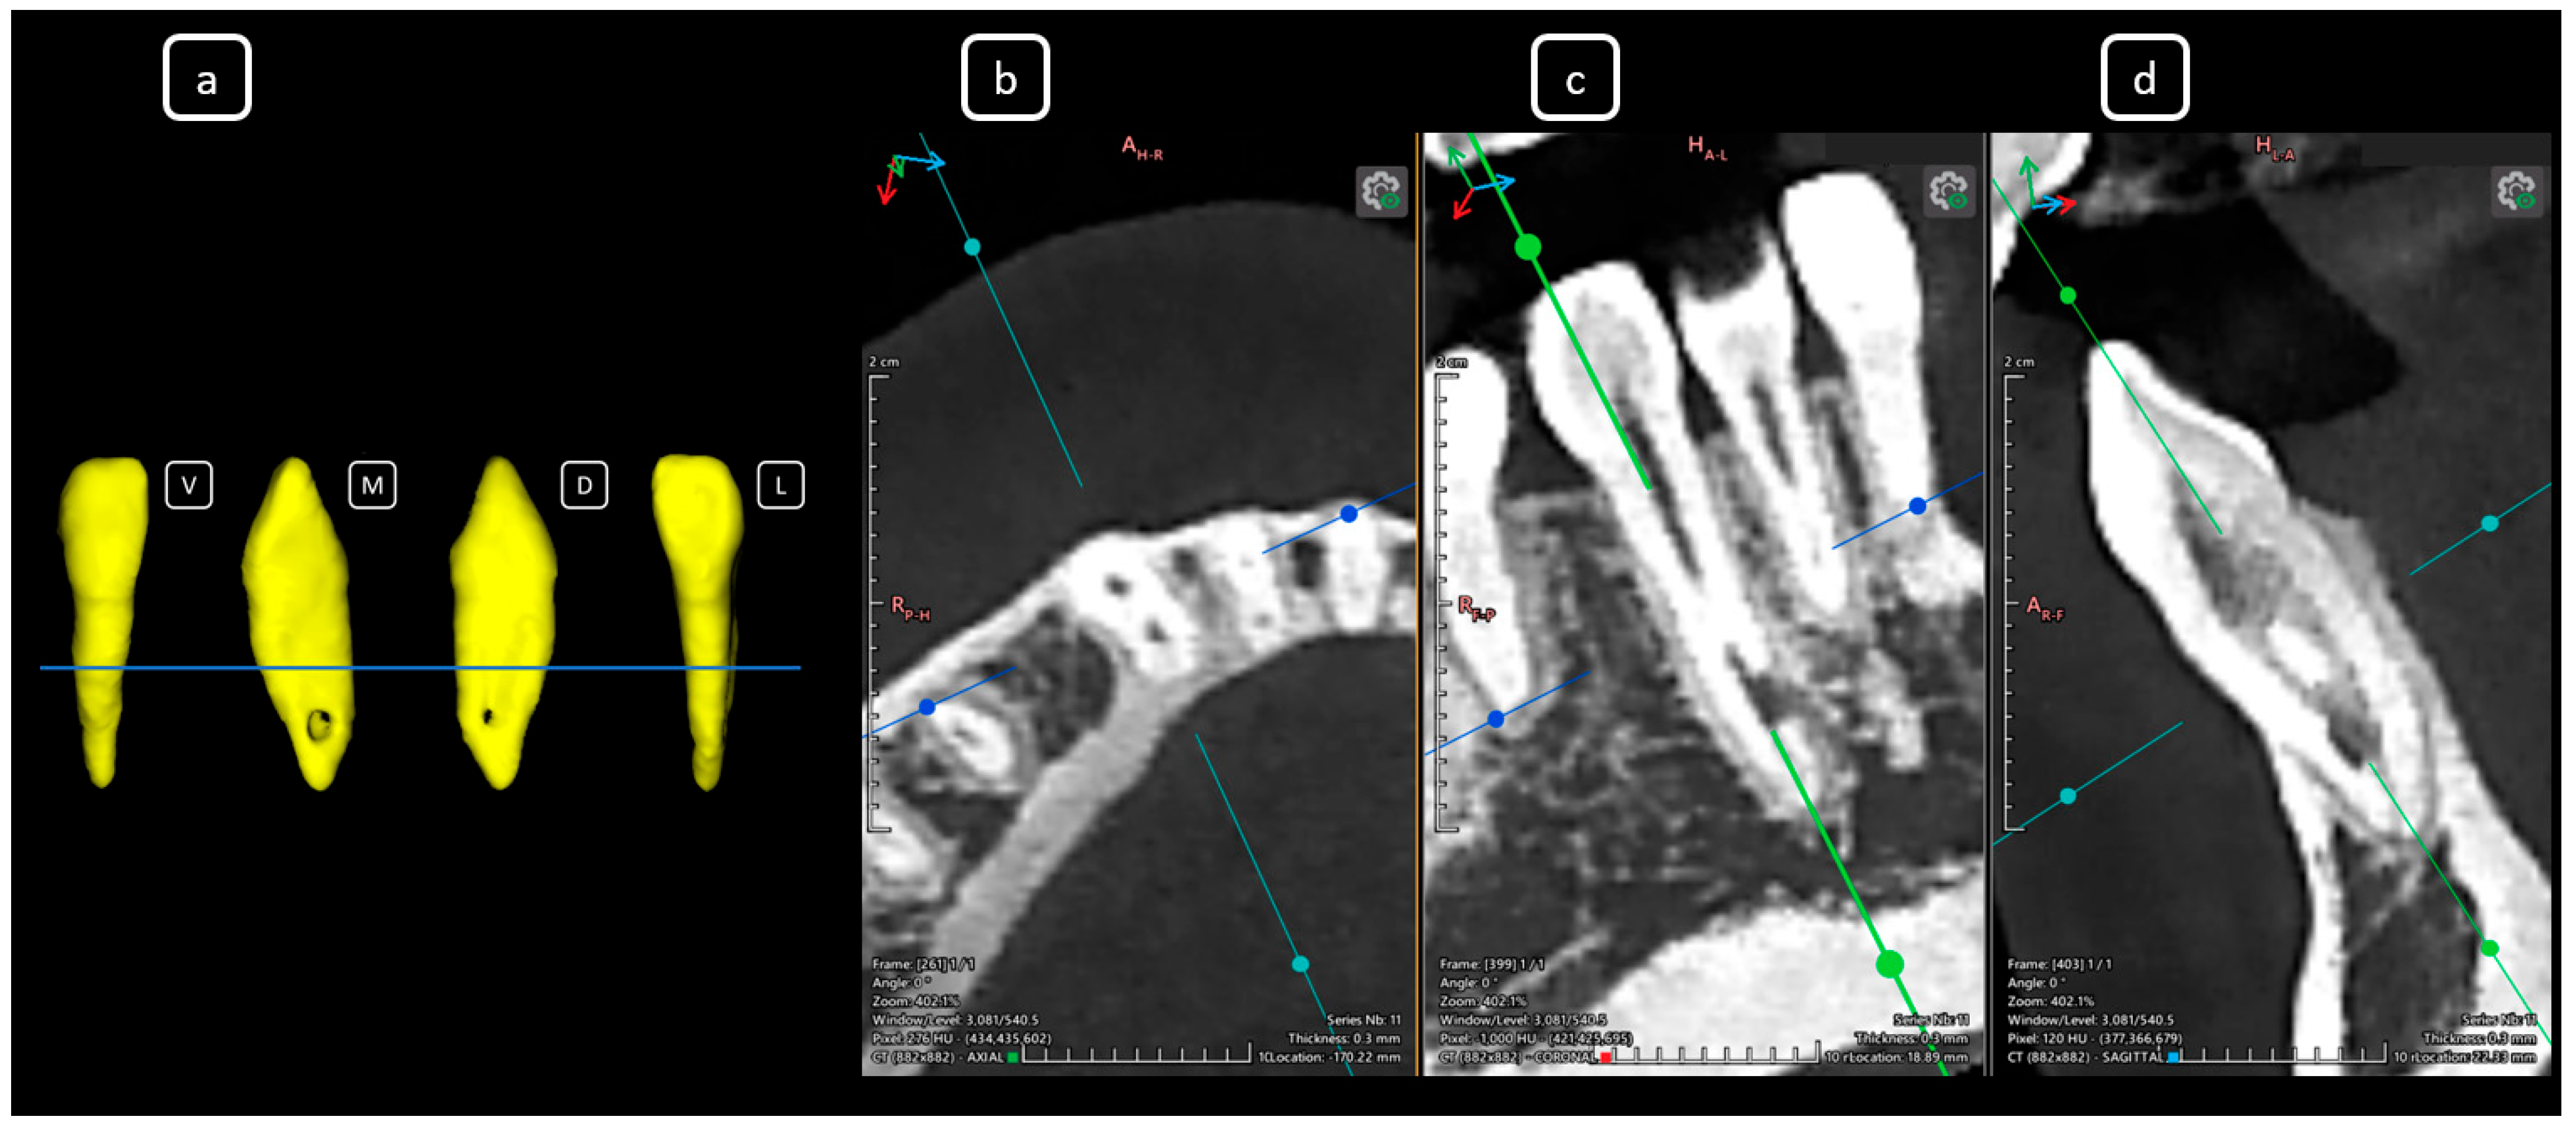

Imaging Findings of Clinical Significance in Endodontics During Cone Beam Computed Tomography Scanning of the Upper Airway—The Anterior, Bilateral, C-Shaped, Dual of Mandibular Root Canals: A Brief Case Report

García-Torres, E.; Guerrero-Falcón, D.L.G.; Bojórquez-Armenta, H.A.; Almeda-Ojeda, O.E.; Barajas-Pérez, V.H.; Solís-Martínez, L.J. Imaging Findings of Clinical Significance in Endodontics During Cone Beam Computed Tomography Scanning of the Upper Airway—The Anterior, Bilateral, C-Shaped, Dual of Mandibular Root Canals: A Brief Case Report. Diagnostics 2025, 15, 3157. https://doi.org/10.3390/diagnostics15243157